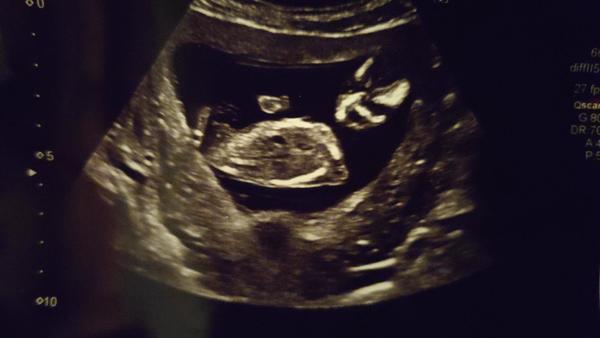

@juliemichal co myslíte, holcicka či chlapec ?

@lilianapul30 pravje jsem jsi to myslela take ale je to holcicka ale dekuji 😊